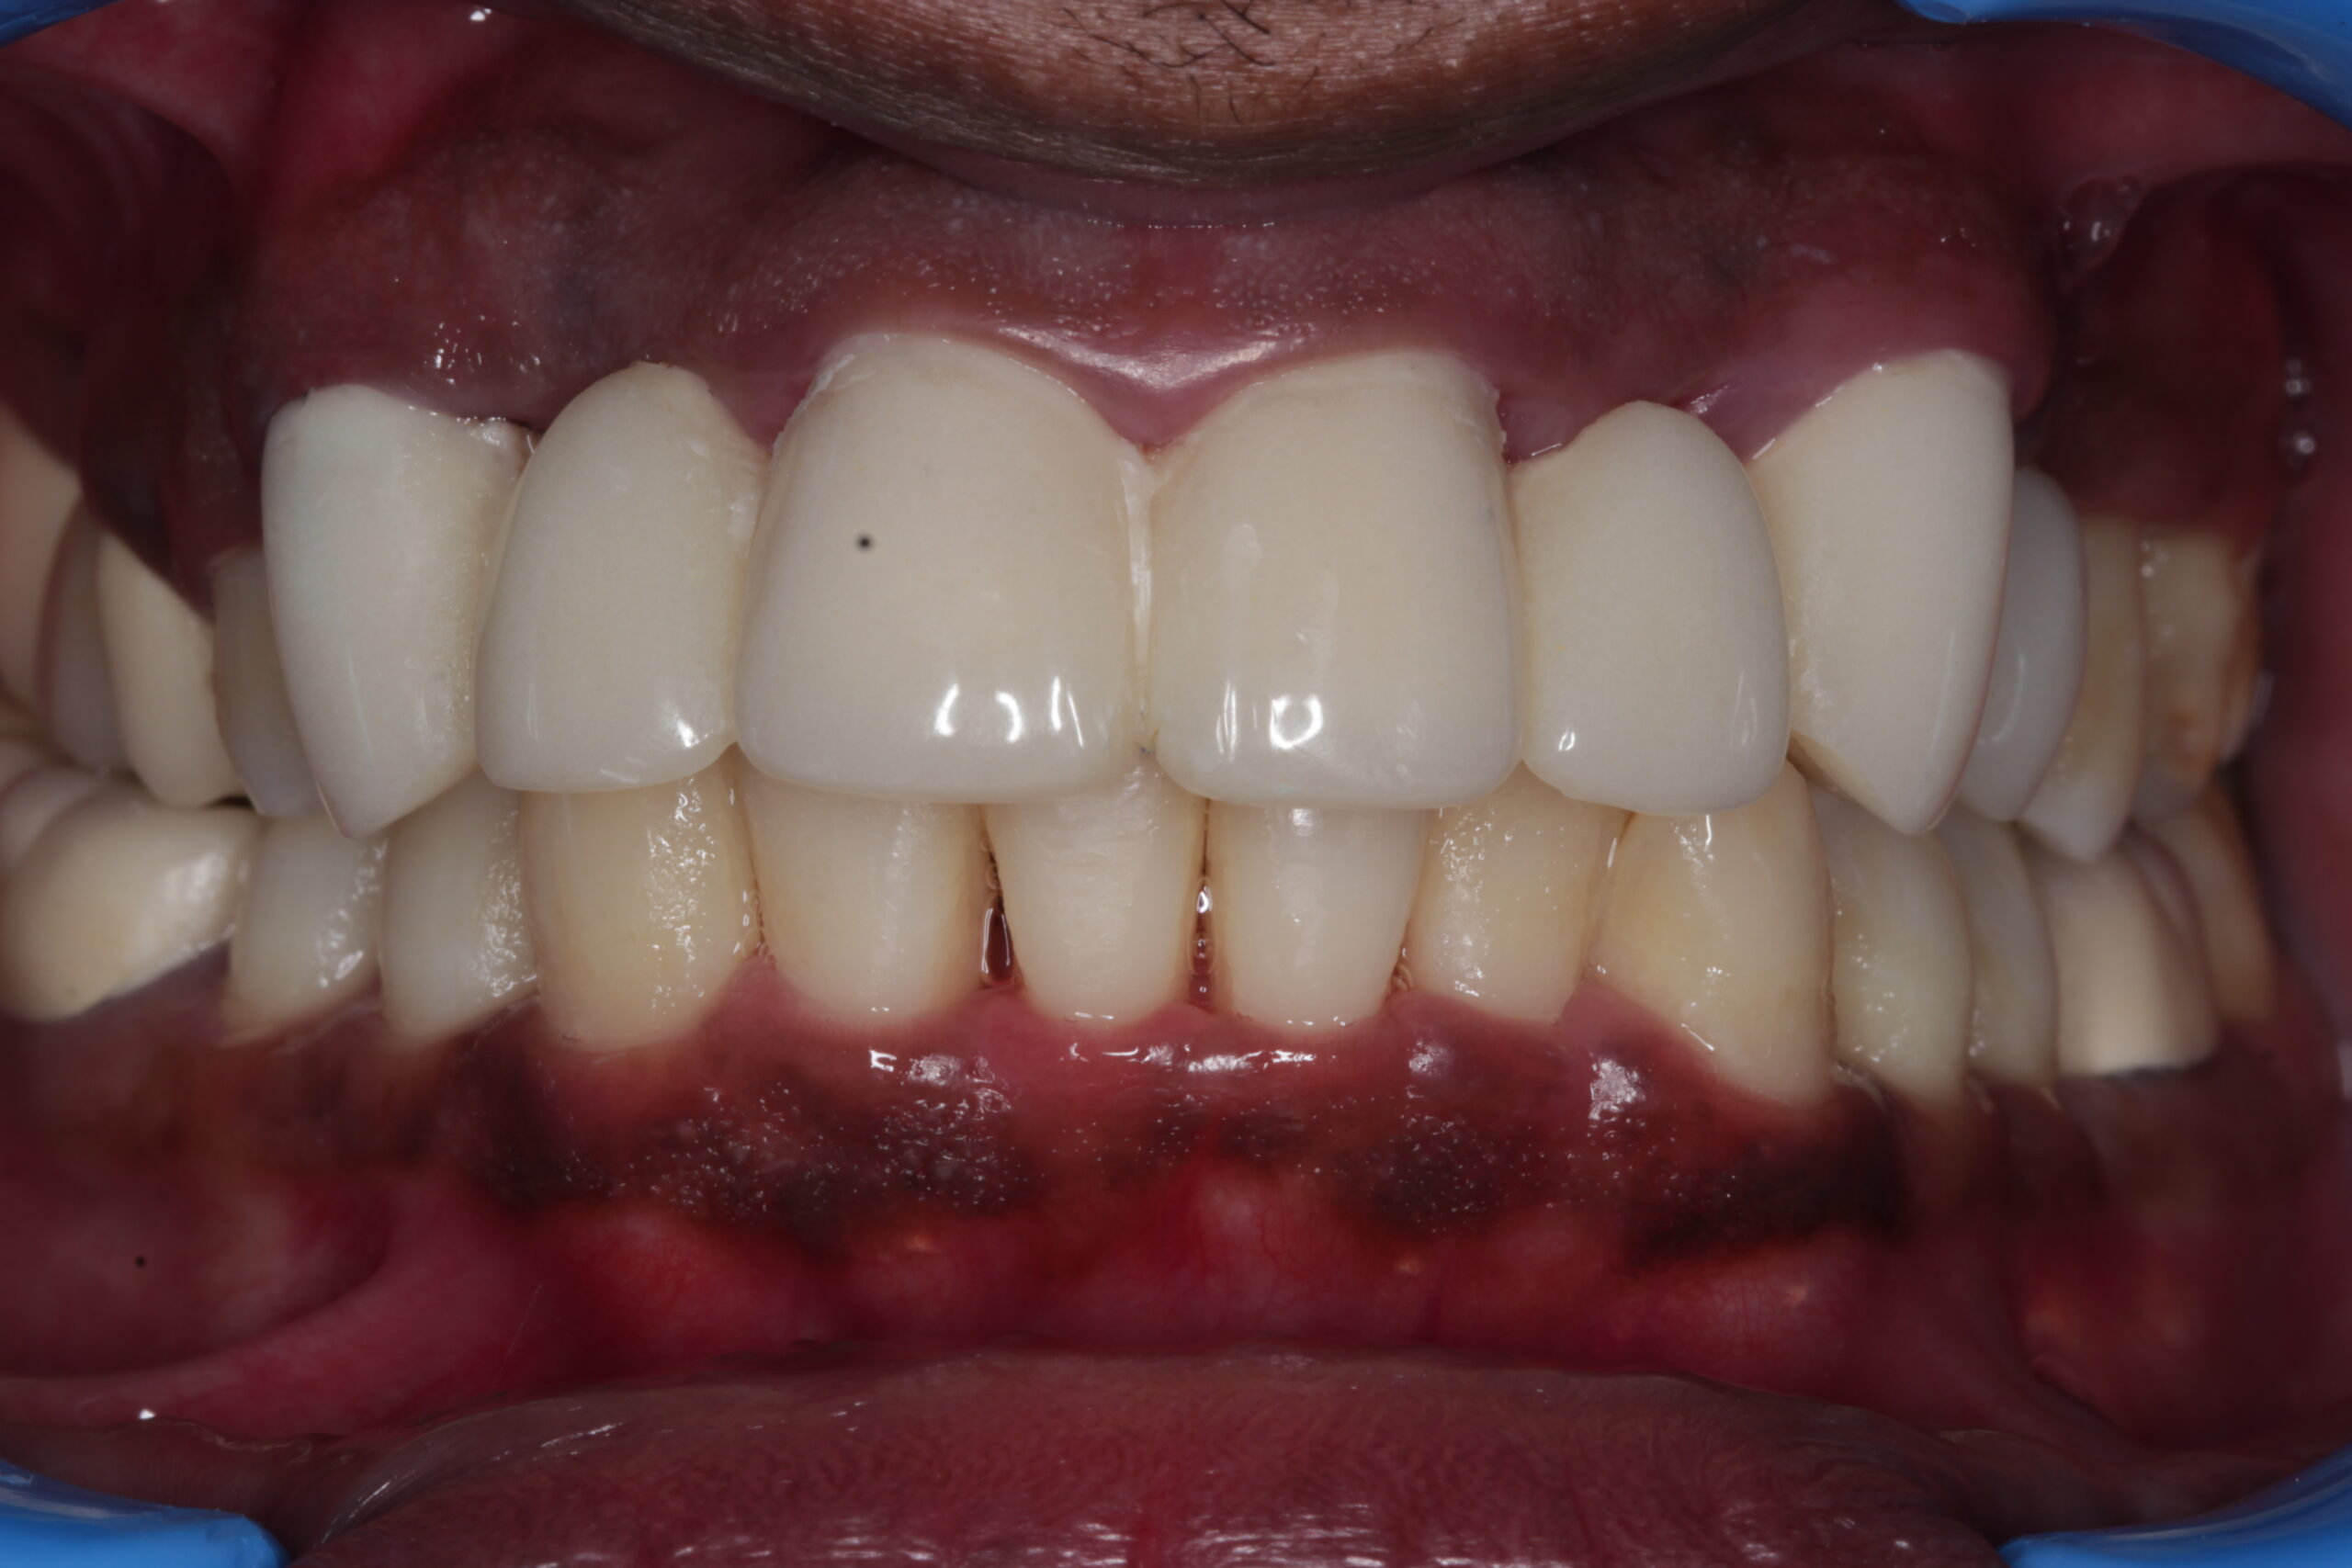

• Improved Appearance: Flap surgery can restore the appearance of the gums and teeth, addressing issues such as gum recession.

• Reduces inflammation and improves gum appearance

• Enhances your smile by maintaining healthy gums